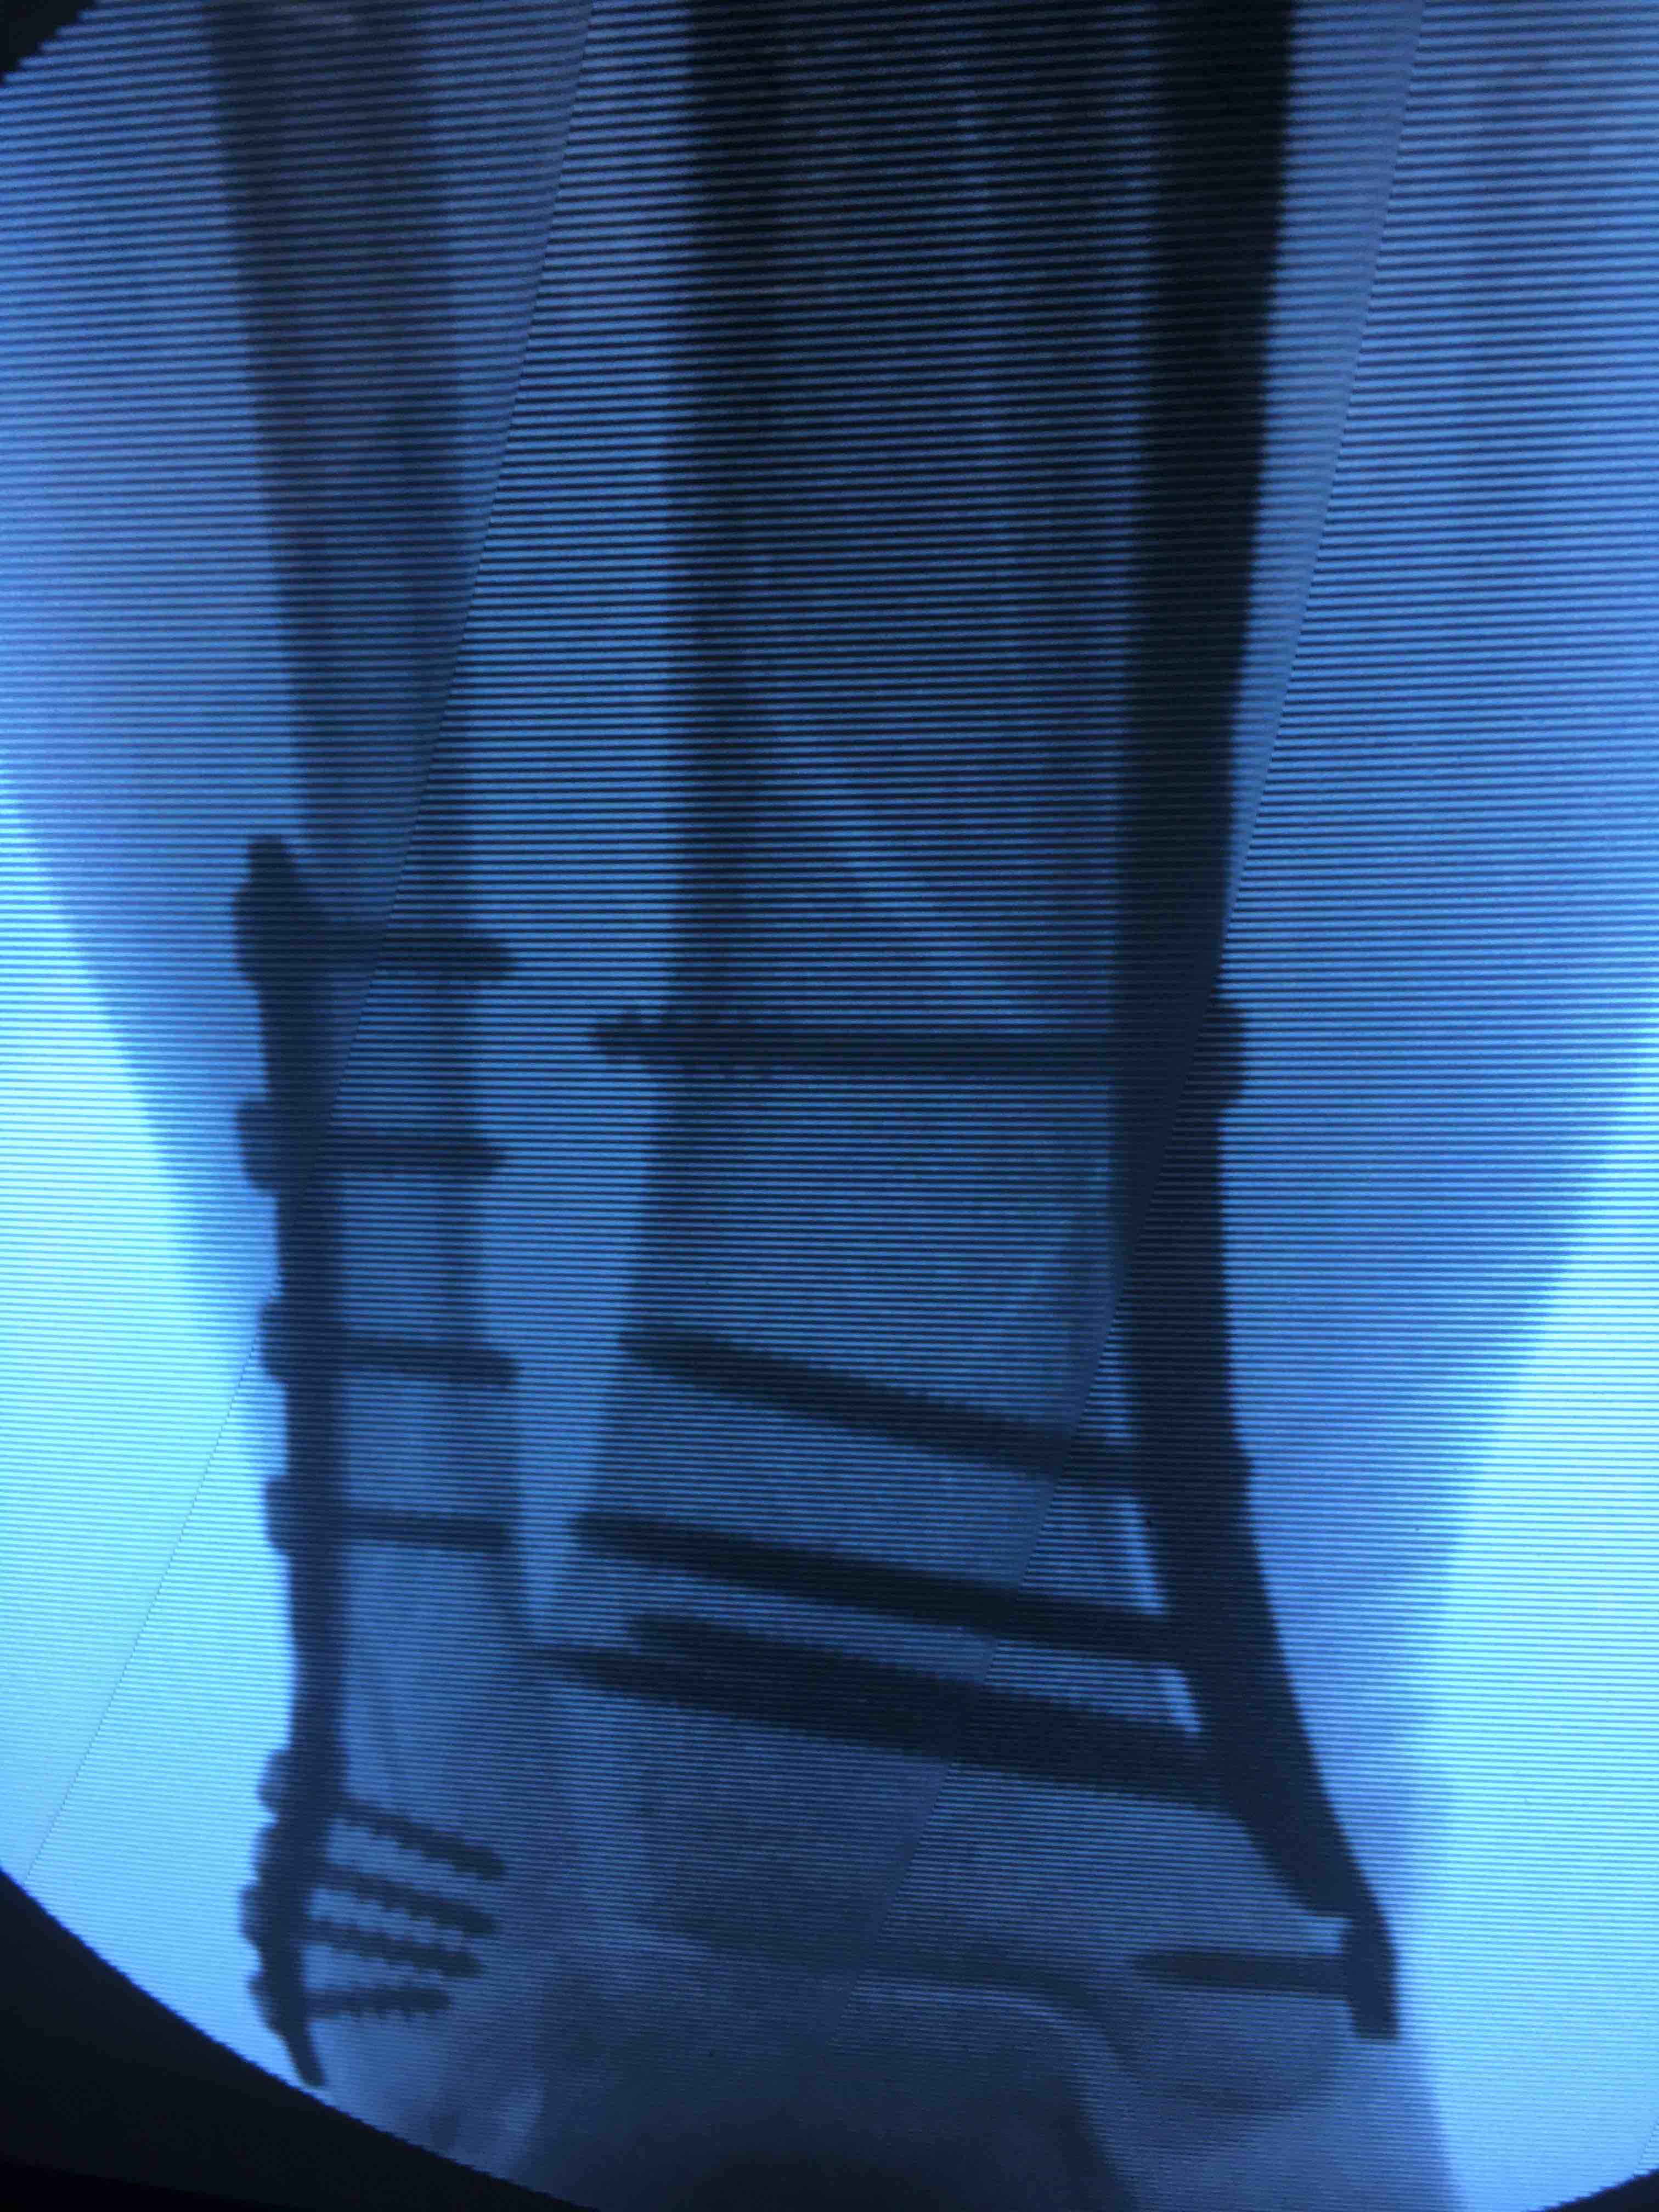

胫腓骨下段骨折(微创固定)

摔伤后右小腿肿痛,活动受限1小时入院。既往身体健康,无特殊不良嗜好。

生命体征平稳,心肺复未见明显异常。右小腿肿胀,局部皮色皮温正常,压痛及叩痛阳性,可及骨擦音,活动受限,末梢血运感觉正常。

在腰麻下行切复内固定术,术后抗炎,消肿对症治疗。